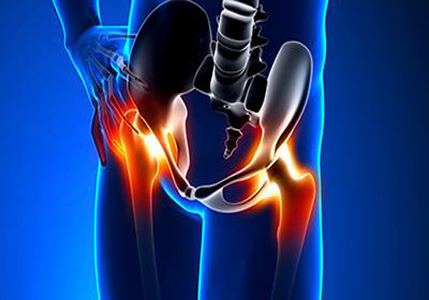

股骨头坏死患者肌肉萎缩主要是因为大腿的血液供应减少造成的。股骨头坏死的发生虽然原因各个有不同,但是发病肌机理都是导致股骨头周围血液循环障碍。

血液循环障碍不但会造成股骨头坏死,同时还会造成骨动脉都下肢广泛组织的血液供应减少,下肢肌肉长时间营养不良,就会造成下肢肌肉萎缩。第二种原因是,患肢大腿由于疼痛不经常走路负重,肌肉长时间得不到有效的锻炼肌肉不再发育,肌肉逐渐萎缩变小,造成的废用性肌肉萎缩。